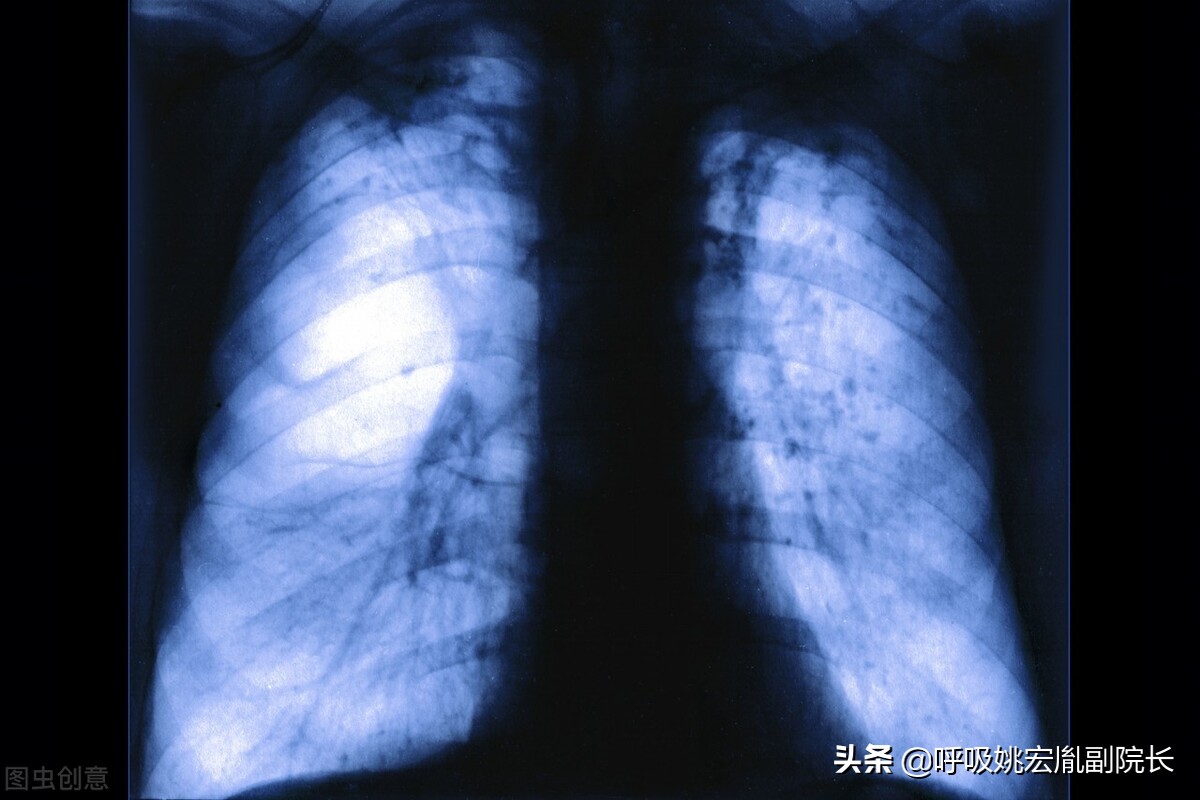

常见的几种肺病:

肺炎:老年肺炎常缺乏明显呼吸系症状,症状多不典型,病情进展快,易发生漏诊、错诊。首发症状为呼吸急促及呼吸困难,或有意识障碍、嗜睡、脱水、食欲减退等。

哮喘:哮病是由于宿痰伏肺,遇诱因或感邪引触,以致痰阻气道,肺失肃降,痰气搏击所引起的发作性痰鸣气喘疾患。发作时喉中哮鸣有声,唿吸气促困难,甚至喘息不能平卧为主要表现。

肺气肿:肺气肿是指终末细支气管远端的气道弹性减退,过度膨胀、充气和肺容积增大或同时伴有气道壁破坏的病理状态。按其发病原因肺气肿有如下几种类型:老年性肺气肿、代偿性肺气肿、间质性肺气肿、灶性肺气肿、旁间隔性肺气肿、阻塞性肺气肿。

肺结节:肺结节是指在肺实质内而不属于正常肺组织的结节状阴影,直径小于3厘米,其中直径小于1厘米的称之为小结节,直径小于3毫米的称之为微结节,而大于3厘米的我们称之为肿块。肺结节可以表现为单独一个,也可以是多个。80%-90%以上的肺结节都是良性的,当然也有一部分结节是恶性的,而少数肺良性结节在随访的过程中可能会出现恶变。

慢阻肺:慢性阻塞性肺病简称慢阻肺,该病是由于一系列的因素(尤其是营养不良,是慢阻肺的“难兄难弟”)导致肺部感染,病情迁延不愈,最终导致慢阻肺,如果没听过慢阻肺,那你一定知道老慢支,慢阻肺就是老慢支的加强版。具有高发病率,高住院率,高死亡率的特点。